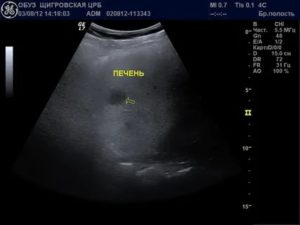

Чаще всего очаги выявляются при УЗИ, но иногда являются случайной находкой при компьютерной томографии или МРТ, когда исследование выполнялось по какой-то иной причине. При этом КТ используется для уточнения размеров, количества, расположения и структуры очагов.

Поскольку печень является достаточно упругим и плотным органом с однородной структурой, почти любые образования и изменения структуры в ней можно выявить с помощью УЗИ, КТ или МРТ, так как они будут иметь другую плотность.

Гиподенсное (или гиподенсивное) образование в печени можно выявить при детальном исследовании на компьютерной или магнитно-резонансной томографии. Основополагающим параметром расшифровки томограммы считается плотность.

Компьютерная томография даёт подробный снимок, на котором видны гиподенсные образования в печени.